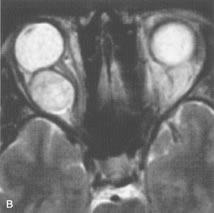

Application of a 90° RF pulse brings the excited nuclei into phase so that the net vector of their magnetic moments is directed perpendicular to the static magnetic field. Shortly thereafter, the magnetic moments of the nuclei spread out and point in different directions, leading to a loss of phase coherence and a resultant decay in signal intensity amplitude. The T2, or spin-spin relaxation time, is the rate of decrease in the signal of these excited nuclei as a result of the interaction and transfer of energy to unexcited adjacent nuclei. T2 ranges from a few milliseconds to a few hundred milliseconds and, for a given tissue, is always less than the Tl relaxation time. T2-weighted orbital images are easily recognized by a high-intensity signal from the vitreous (Fig. 9).5,8,16

Fig. 9. T2-weighted image of the orbits does not delineate normal anatomic details well. The lens can be visualized in the bright vitreous. (Dortzbach RK, Kronish JW, Gentry LR: Magnetic resonance imaging of the orbit. Part II. Clinical applications. Ophthal Plast Reconstr Surg 5:161, 1989)